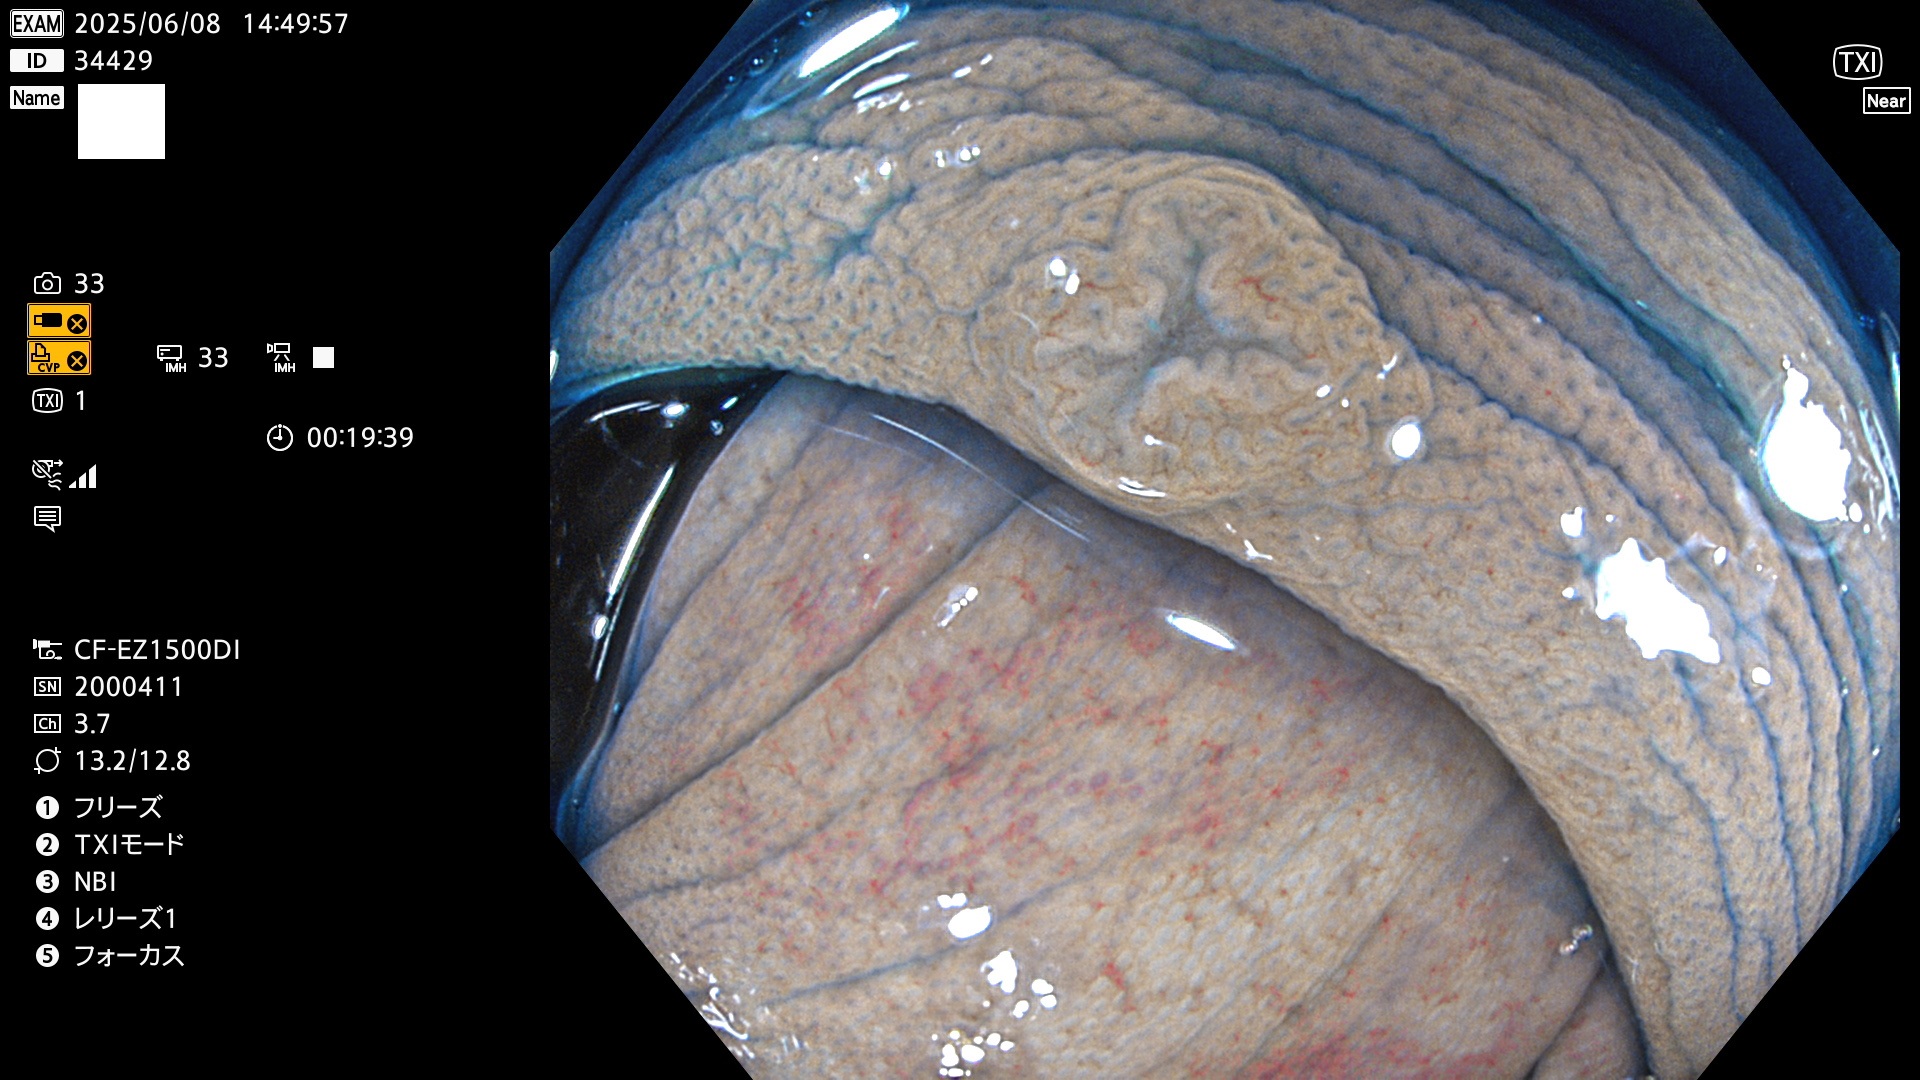

抽出の対象期間 2025年6月5日〜6月8日の4日間(48件の検査)4個 (4/48=8%)